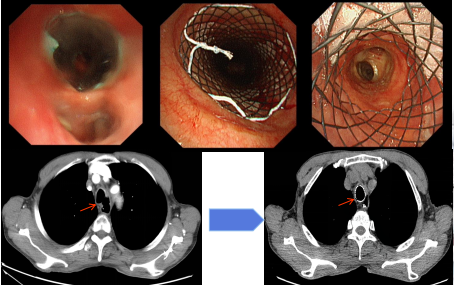

Y型支架置入术

图片18.png